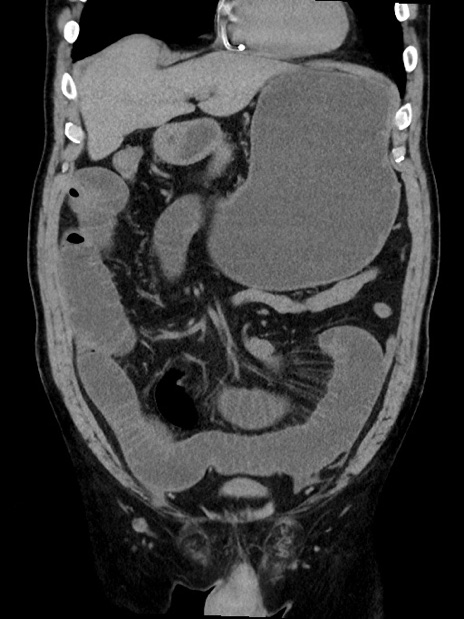

症例35(冠状断像)

【症例】70歳代 男性

【主訴】腹部膨満、嘔吐

【現病歴】昨日より腹部膨満感出現。本日増悪し、仙痛出現。嘔吐あり、受診。

【既往歴】糖尿病、胆摘後

【身体所見】BP 149/80mmHg、HR 74/min、BT 35.9℃、腹部:膨満、軟、圧痛なし。腸雑音減弱あり。上腹部正中切開瘢痕あり。

【データ】WBC 13500、CRP 1.72